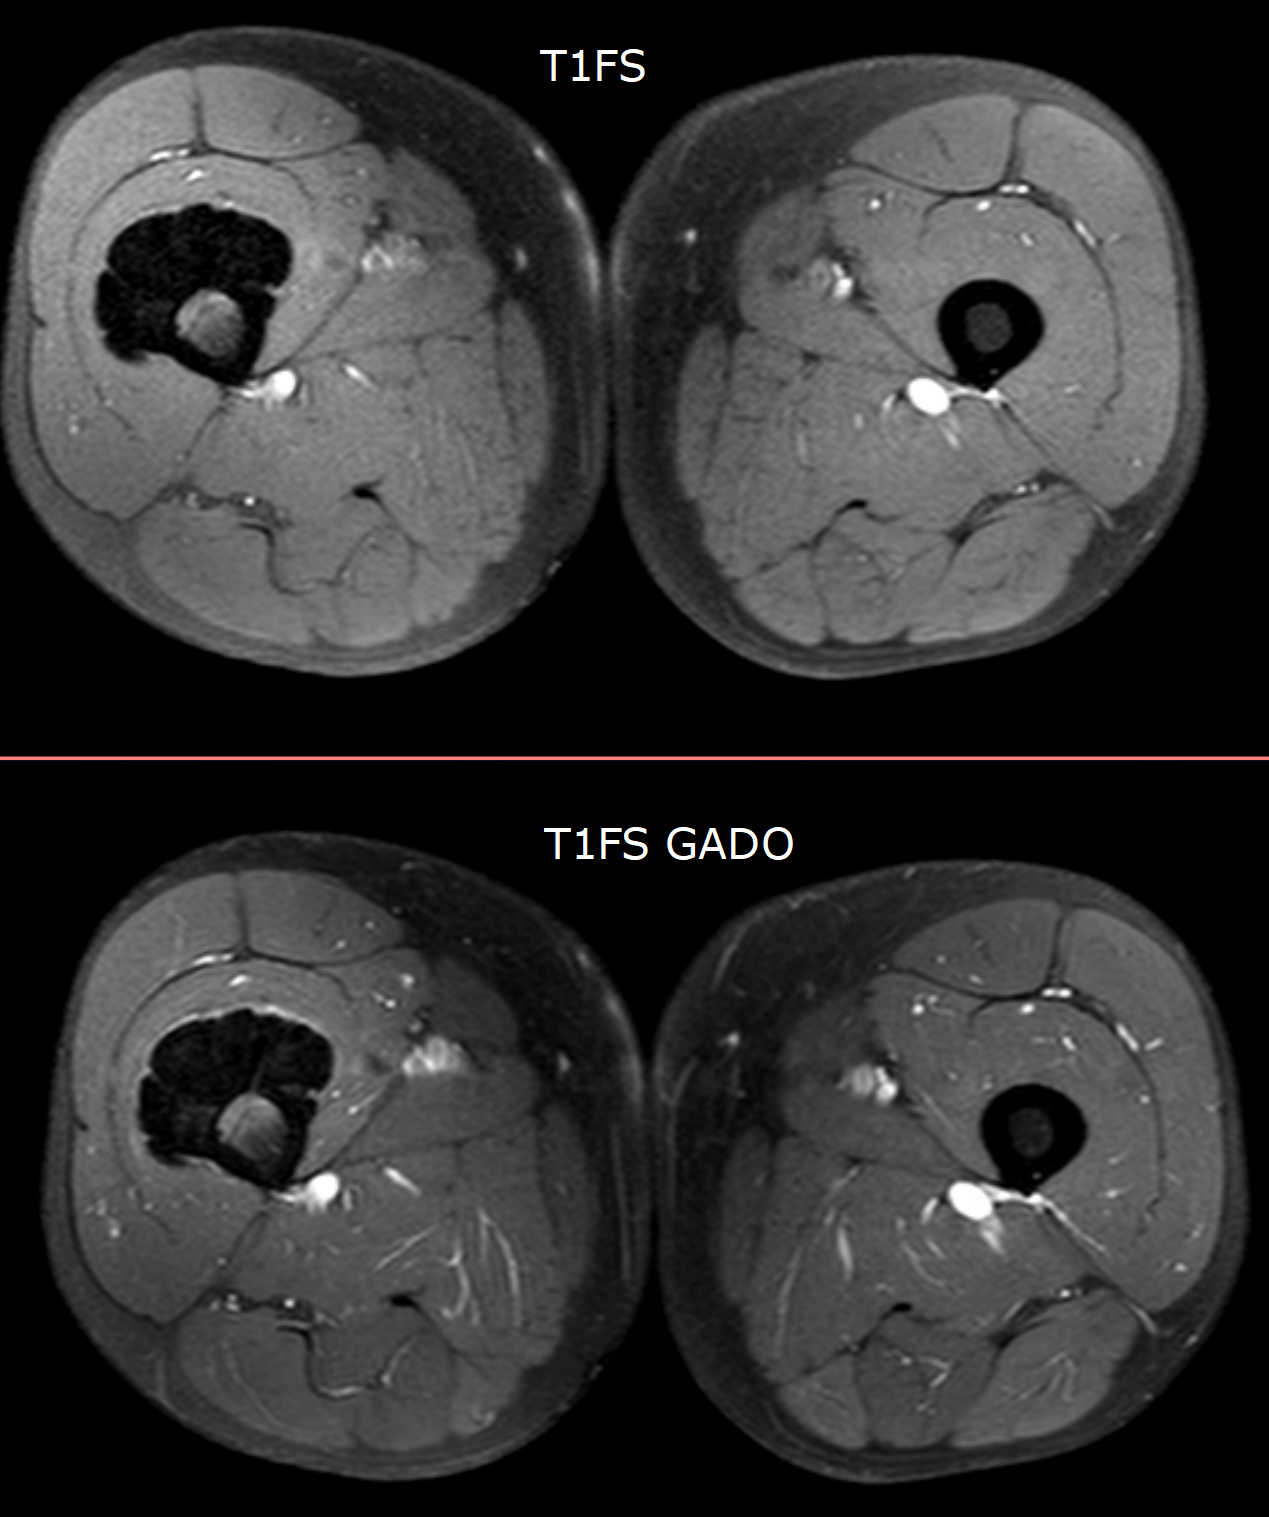

54y M, pain Paraosteal osteosarcoma & melorheostosis Leave a Comment / Cases / By OCAD 54y M,pain Paraosteal osteosarcoma & melorheostosis Opinion please? Ciro [image.png] [image.png] [image.png]